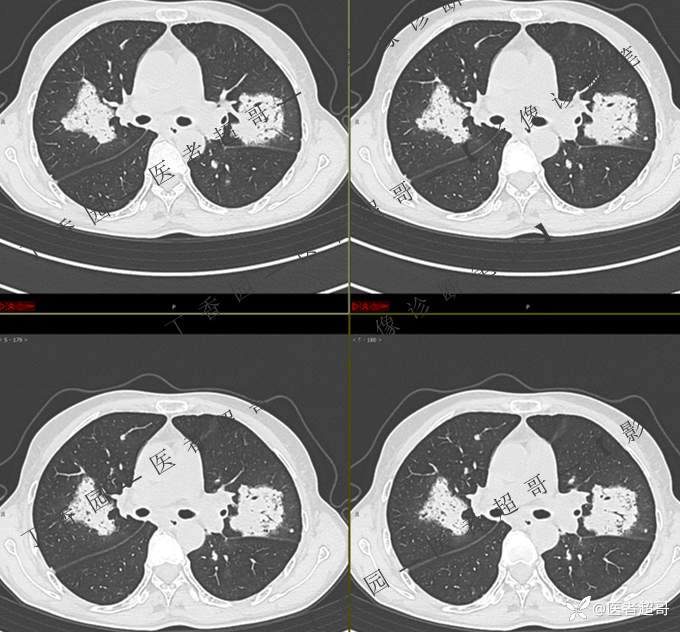

2402胸部影像病例︱持续追踪的一个患者,时间轴较长,闭卷分析,请畅所欲言~~~

女性,57岁

临床治疗一周后复查